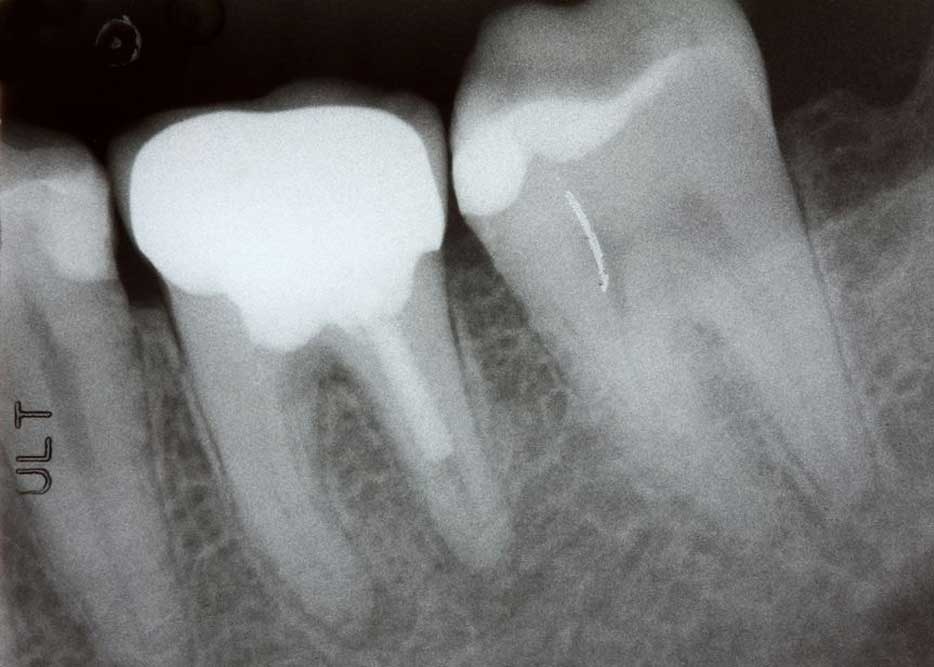

Root Canal Therapy

With root canal therapy, Dr. Carpenter can treat your infected tooth without extracting it. Modern dental techniques make root canal therapy similar to getting a filling, and you can expect a comfortable experience. Root canal therapy can relieve pain, and restore normal biting and chewing.